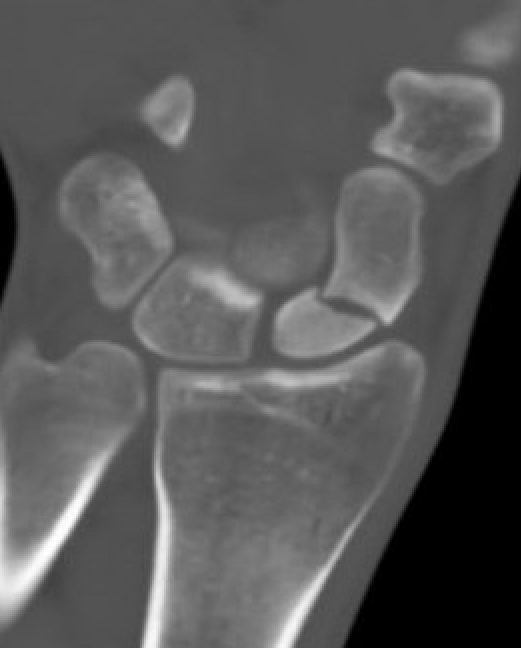

CT

Increased sclerosis of the proximal pole

Fragmentation and collapse of the proximal pole